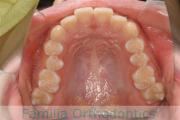

No.22V-449

- 主な症状:

- 上顎前突

- その他の症状:

- 叢生

- 年齢:

- 14歳

- 性別:

- 男性

- 抜歯部位

- 上:

- 44

- 下:

- 8448

- 主な使用装置:

- FEA

- 治療にかかった費用:

- 87万円

歯並びをきれいにしたいということで来院されました。上下左右から小臼歯を抜歯して、マルチブラケット法を行っています。2年弱、25回程度の通院が必要でした。

かなり強い叢生(でこぼこ、凹凸、ガタガタ)ですので、保定をしっかりしないと後戻りのリスクがあります。

- ≫治療前

-

上顎

下顎

前歯の関係など